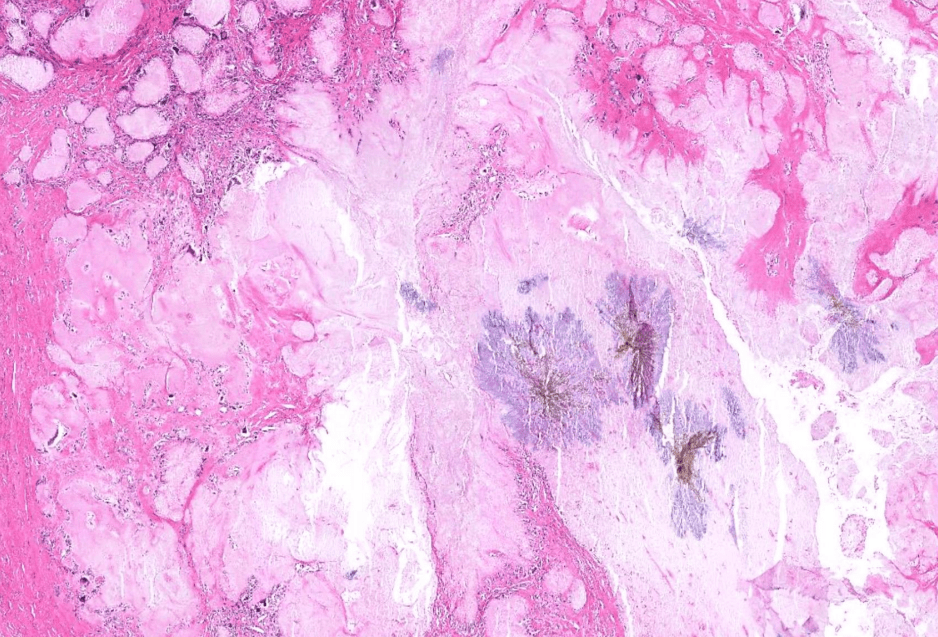

breast cancer

dyslipidemia

hepatocellular carcinoma